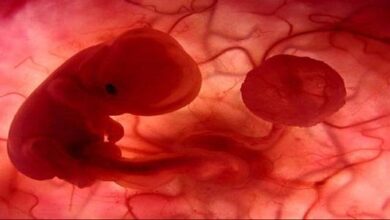

- الشهر الأول: حيث تنمو البويضة المخصبة، ويحيط بها كيس مملوء بسائل أمنيوسي (بالإنجليزية: Amniotic Sac)، والذي يعمل على حماية البويضة أثناء تطورها. كما تبدأ المشيمة بالتطور، لإمداد الجنين بالتغذية اللازمة. ومع نهاية الشهر الأول، يتكون القلب بشكله البدائي، ويبدأ بالنبض بمعدل 65 نبضة في الدقيقة الواحدة.

- الشهر الثاني: حيث تبدأ معالم وجه الجنين بالتكوّن بشكل أوضح، وتبدأ البراعم التي ستنمو لتشكل أطراف الجنين بالظهور بشكل تدريجي، كما يكون حجم الرأس كبير نسبة لحجم الجسم خلال هذا الشهر. ويبدأ الجهاز العصبي، والهضمي، والعظمي بالتطور خلال هذا الشهر.